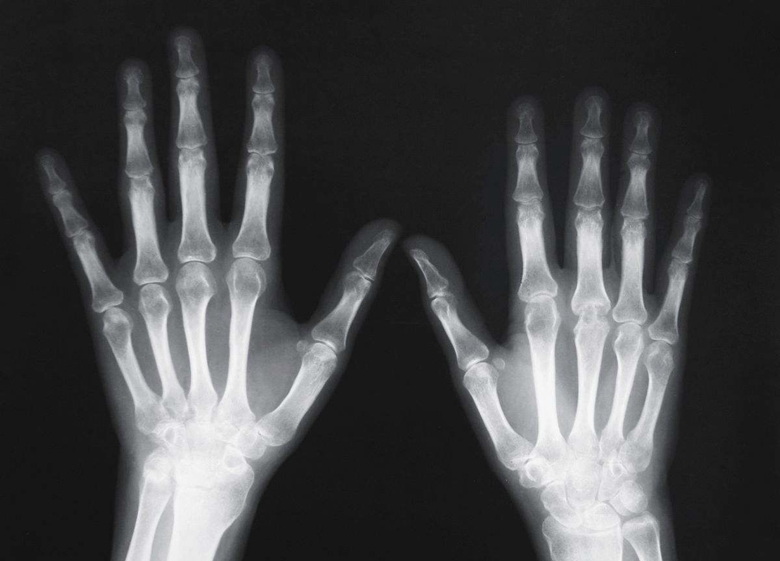

X線檢查作為輔助檢查方法之一。臨床醫(yī)學(xué)上常用的X線檢查方法有透視和攝片兩種。

攝片能使受檢部位結(jié)構(gòu)清晰地顯示于X線片上,并可作為客觀記錄長期保存,以便在需要時隨時加以研究或在復(fù)查時作比較。必要時還可作X線特殊檢查,如斷層攝影、記波攝影以及造影檢查等。選擇何種X線檢查方法,必須根據(jù)受檢查的具體情況,從解決疾?。ㄓ绕涫枪强萍膊。┑囊蠛团R床需要而定。X線檢查僅是臨床醫(yī)學(xué)輔助診斷方法之一。